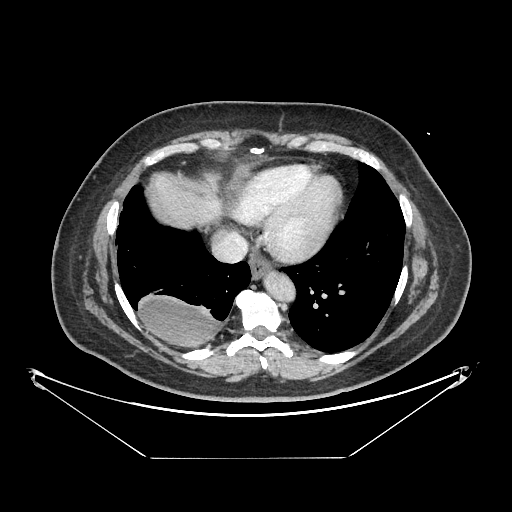

Original VENOUS CT scan

Full window (WL 1023.5, WW 4095 β†’ Low βˆ’1024, High +3071)

Actual HU range: [-160.0, 240.0]

Lung window (WL -600, WW 1500 β†’ Low βˆ’1350, High +150)

Actual HU range: [-160.0, 150.0]

Mediastinum window (WL 40, WW 400 β†’ Low βˆ’160, High +240)